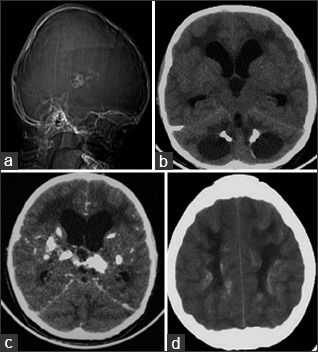

Компьютерная томография показала признаки лакунарного черепа (определялись группы круглых, овальных или пальцевидных вдавлений на внутренней поверхности свода черепа, разделенные ребристыми выростами нормальной костной ткани в самых толстых частях лобной, теменной и верхней затылочной костей - характерный признак внутриутробного повышения внутричерепного давления или нарушения костеобразования - прим.пер.), а также обширные области интракраниальных кальцинатов, которые распространялись билатерально на глубокия* ядра мозжечка, границу белого и серого вещества, таламусы, область базальных ядер и капсулы.

а: на топограмме, которая проводится для разметки сканирования, хорошо видны лакунарный череп и интракраниальные кальцинаты.

b: КТ без контрастного усиления показала двусторонние кальцинаты в зубчатом ядре мозжечка;

с: несимметричная двусторонняя обширная кальцификация в области базальных ядер и внутренней капсулы, таламусов и

d: границы серого и белого вещества

Аксиальные КТ-сканы (A, B) показывают двусторонние кальцинаты в области таламусов и хвостатых ядер, а также множественные кисты в обеих гемисферах мозга. Т2ВИ томограмма (С) показала диффузный патологический МР сигнал от белого вещества при сохранном сером веществе мозга. МРТ после введения контрастного препарата (D) показала, что киста в левой лобной доле демонстрирует неоднородное кольцевидное контрастное усиление.